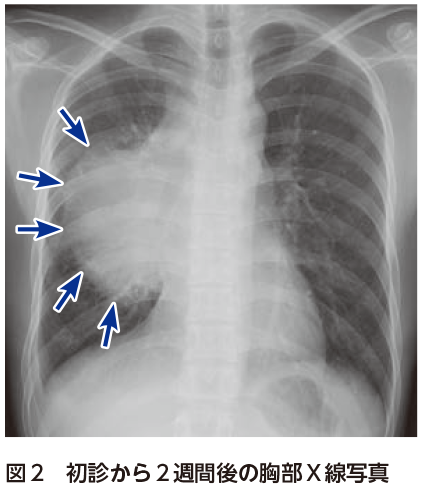

解答 解説 微熱 倦怠感 吸気時の胸痛を主訴に受診した歳代男性 実践 画像診断q A 羊土社 レジデントノート 羊土社